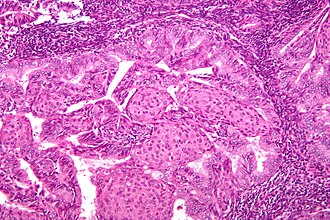

Endometrioid endometrial adenocarcinoma. H&E stain. | |

Endometrioid endometrial carcinoma, abbreviated EEC, is the most common type of endometrial carcinoma. It is strongly associated with obesity.

Microscopic

Features:

- Atypical (ovoid) glands with - one of the following four:[3][4][5]

- Desmoplastic stromal response.

- Confluent cribriform growth. †

- Extensive papillary growth. †

- Severe cytologic atypia. †

- Endometrioid features:

- +/-Low-grade nuclear features.

- Squamous metaplasia - very common.